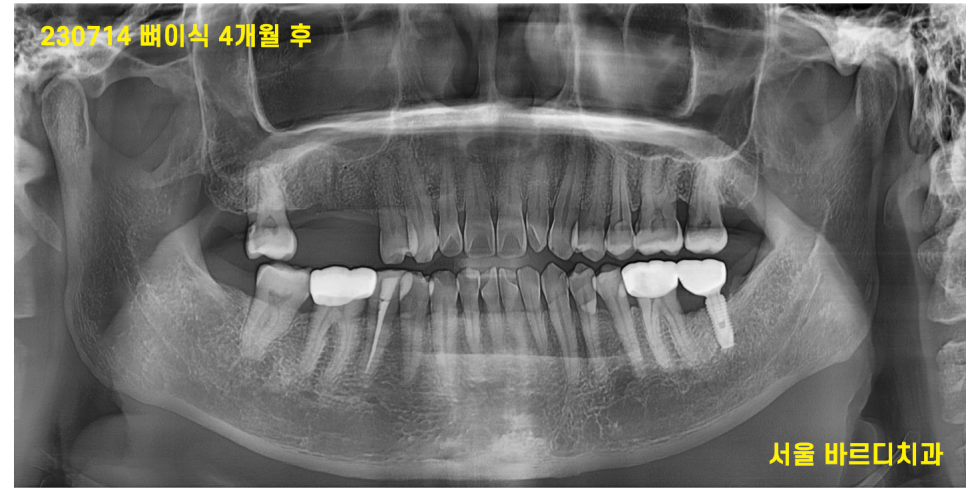

230714

두달 뒤 고덕동 치과 재방문

이때도 수술하지 못했습니다.

2달을 또 기다렸습니다.

뼈이식만 해놓고 6개월을 기다린거죠~

아직 임플란트는 심지도 못했는데ㅠㅠ